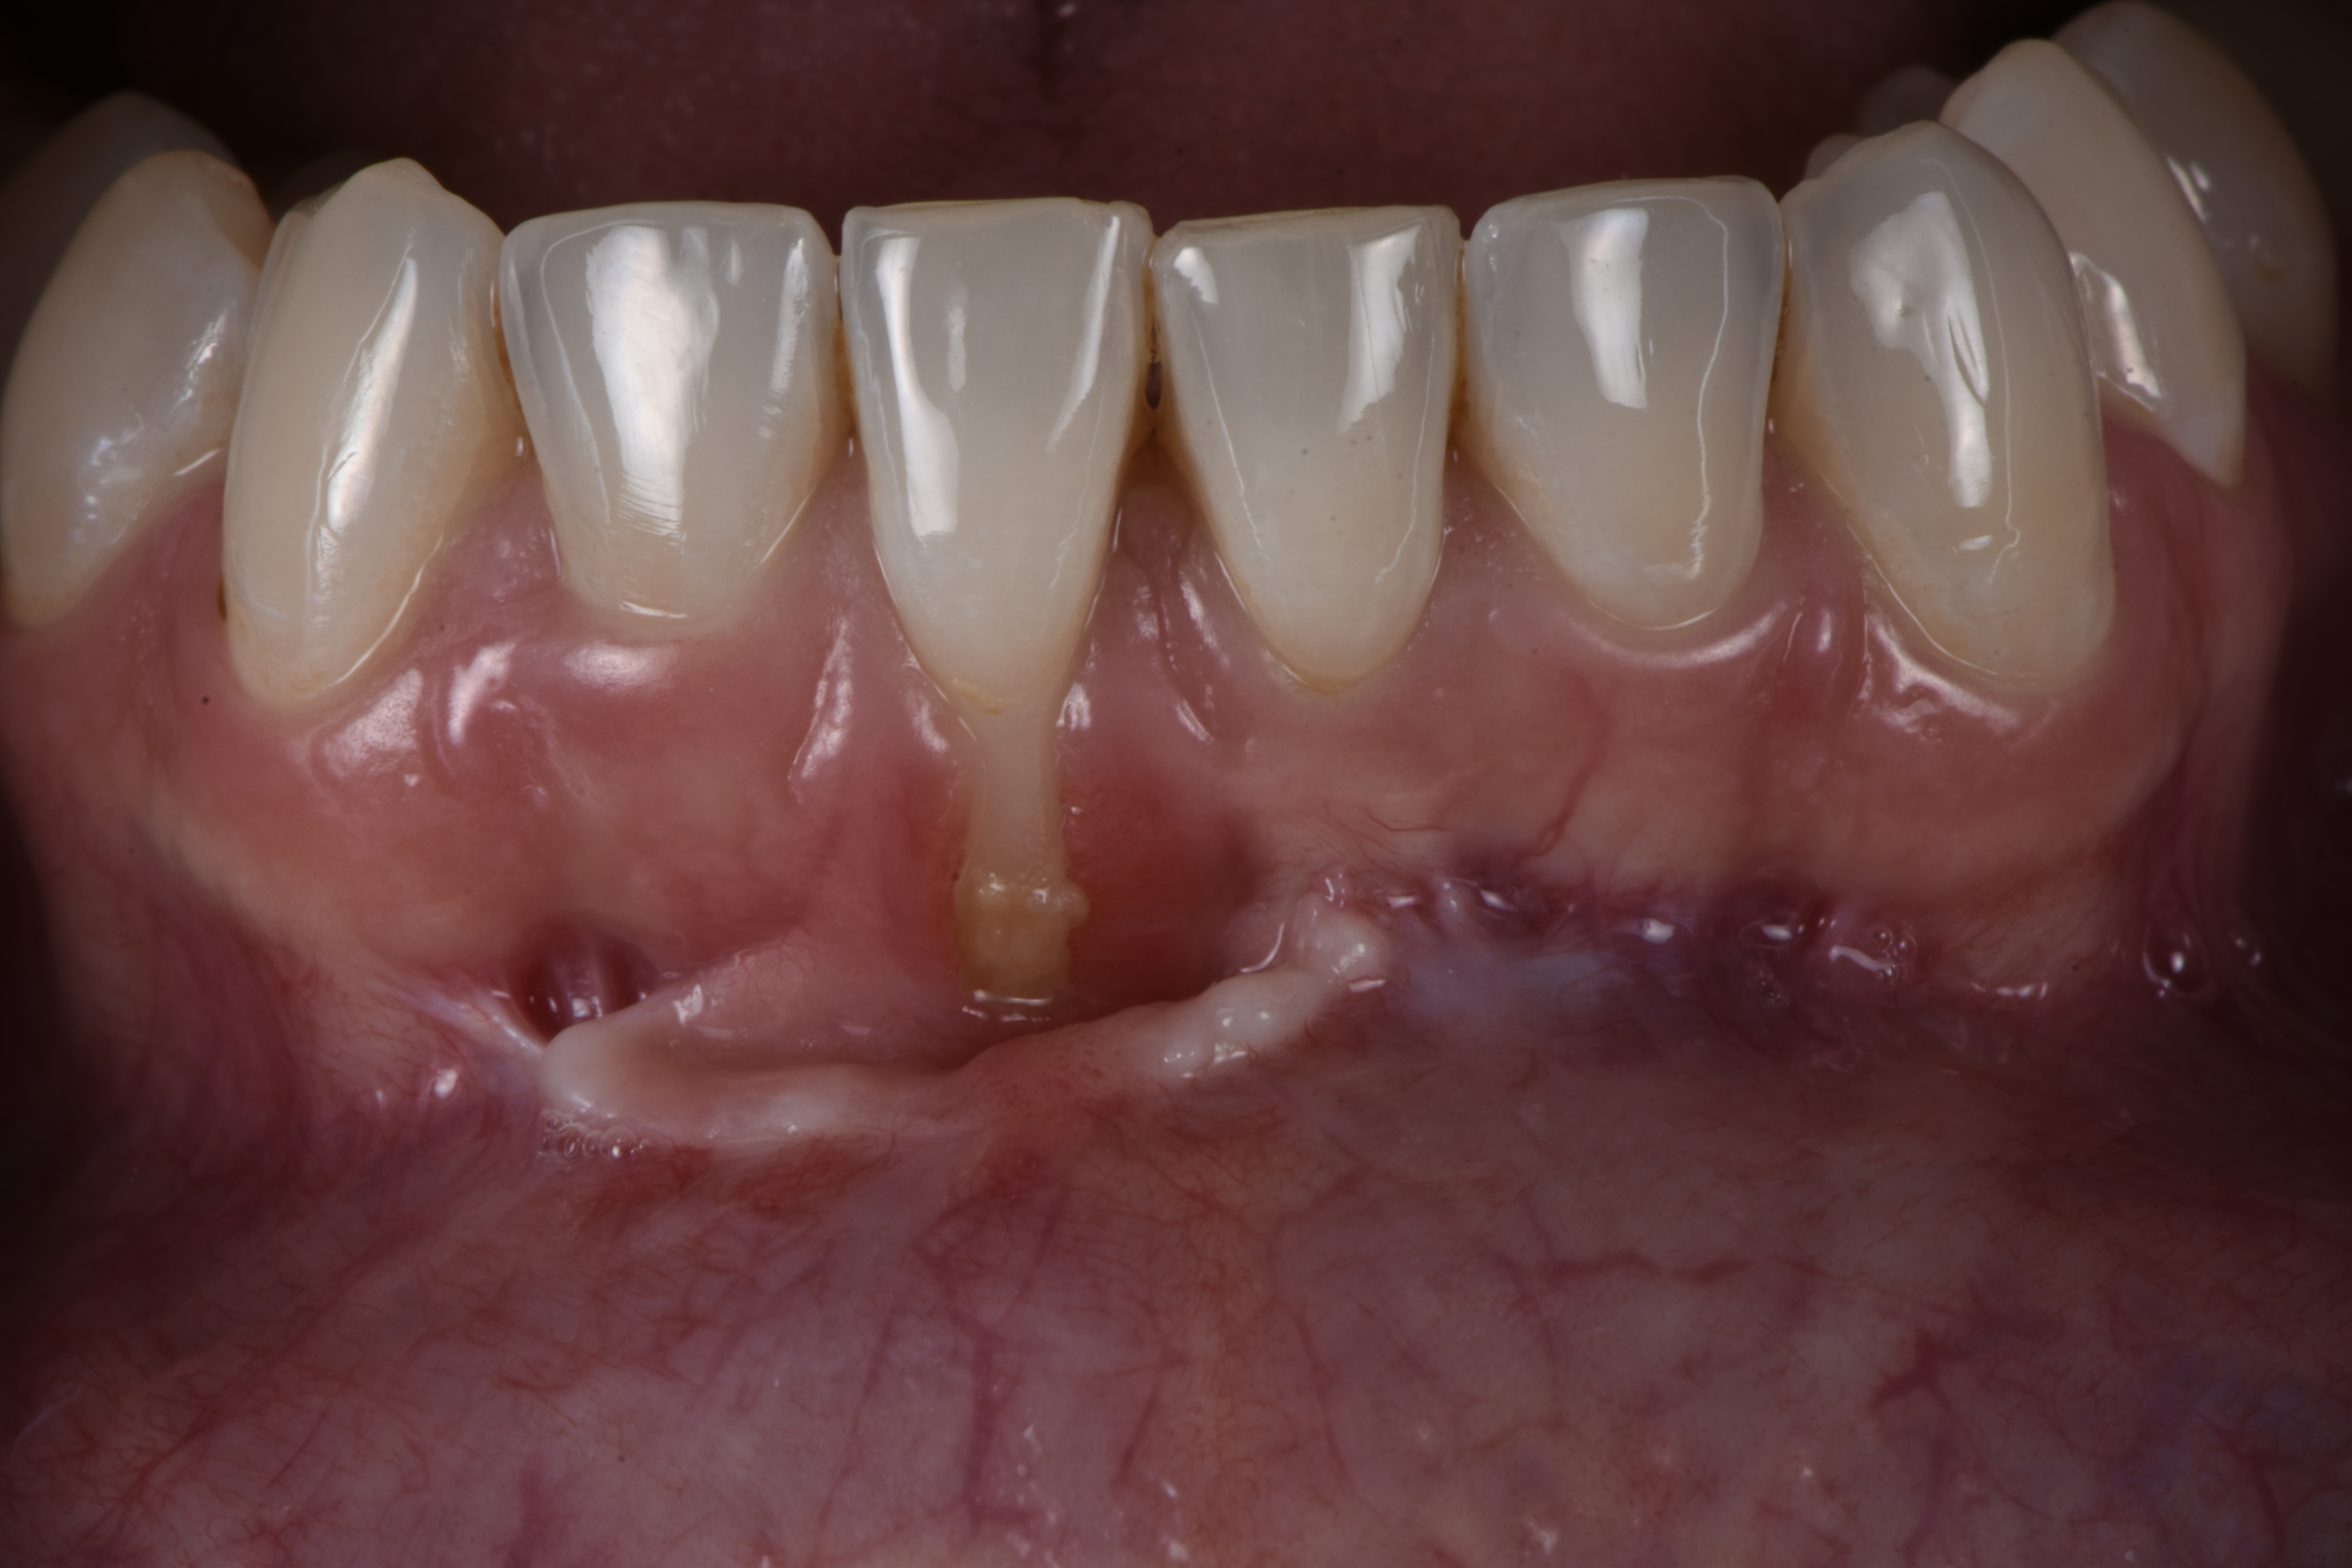

Una vez que hemos perdido encía y se ha quedado la raíz dental expuesta, podemos realizar cirugía mucogingival para volver a recuperar la estética y salud de nuestro periodonto.

Casos clínicos realizados por el Dr. Alfonso García

Déspues

Caso 2